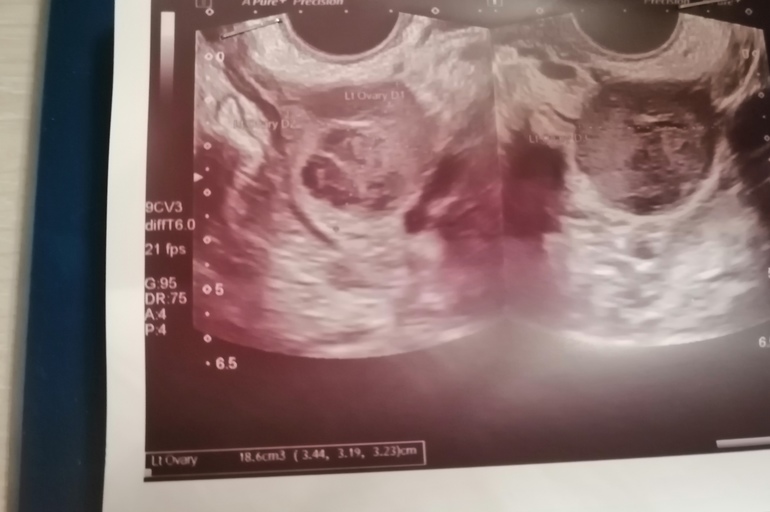

Александра, а Вы можете по моему УЗИ определить тип кисты?

Я не профессионал. Нужно описание. Если с мелкодисперстным содержимым (его еще называют «шоколадным») то это эндометриома скорее всего. А врач что вообще говорит?

У меня на УЗИ сразу сказали, что эндометриодные кисты. После лапароскопии все подтвердилось. При таких кистах анализ крови на СА-125 бывает повышен.

эндометриоидная киста имеет "шоколадное" содержимое со взвесью. Если аппарат нормальный, но видно. А отправляют кисты на анализ всегда для исключения наличия атипичных клеток. Вот это на глазок точно не определить.